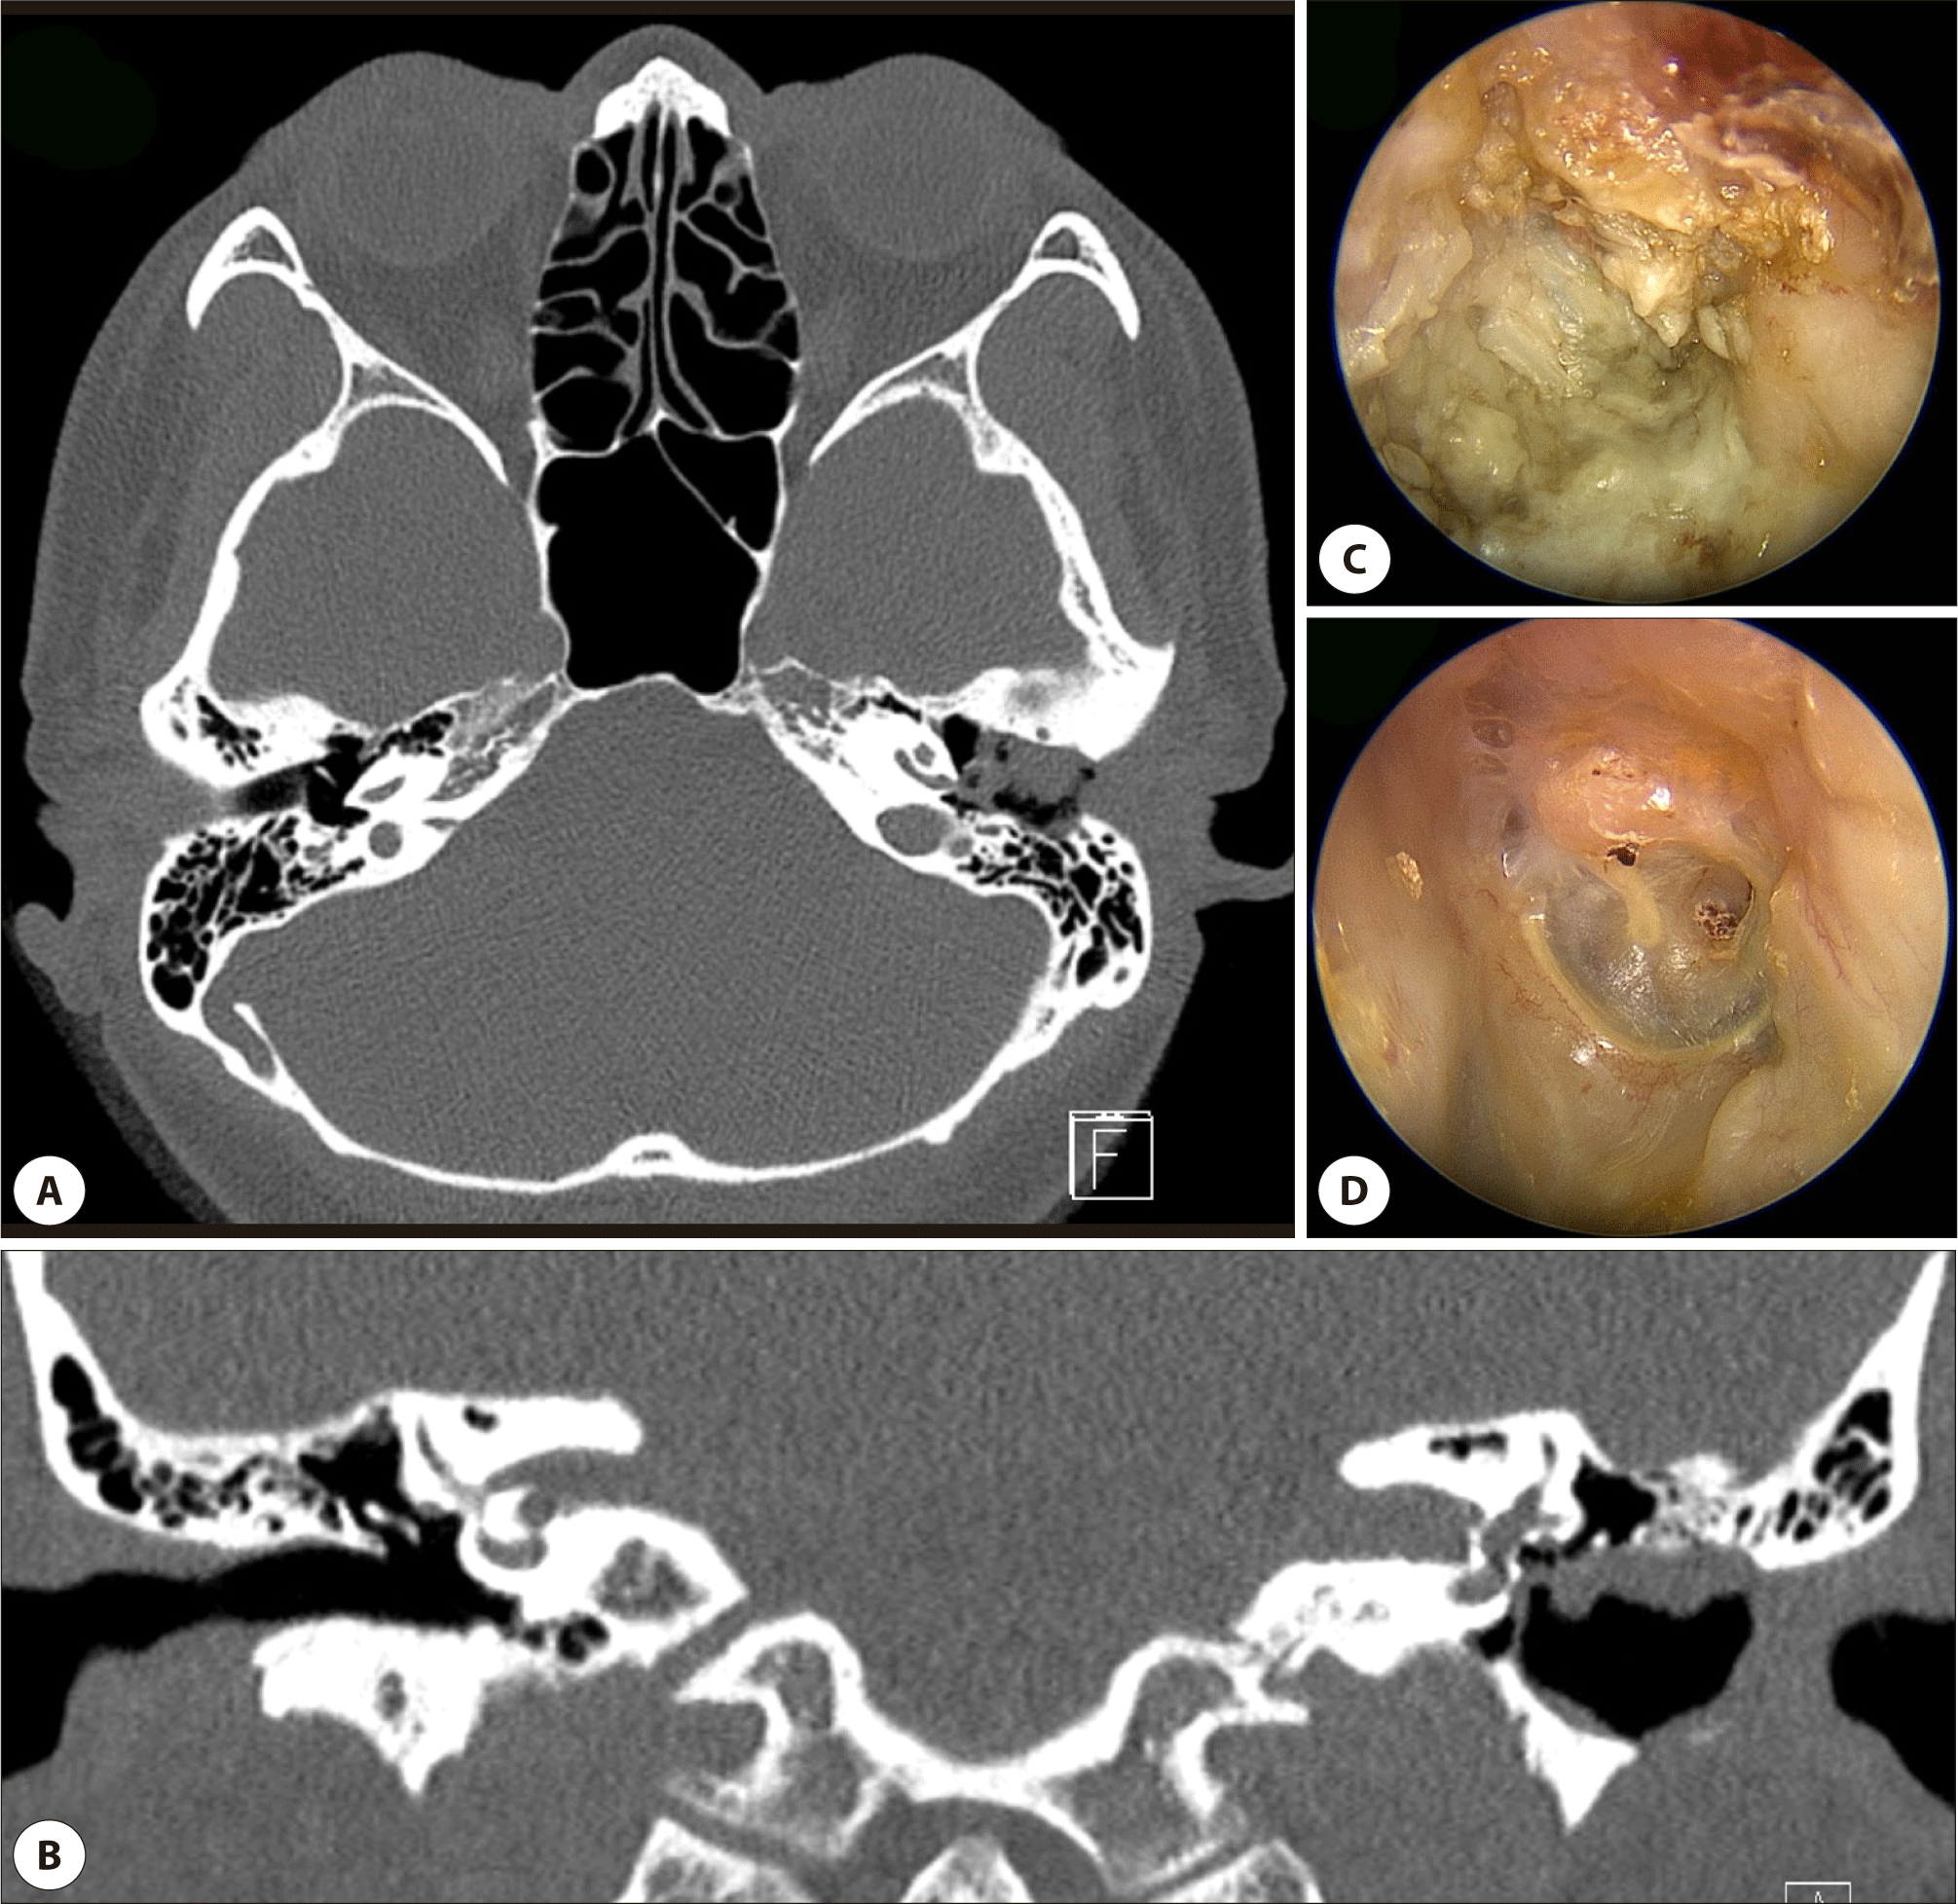

Fig. 1. External auditory canal cholesteatoma (EACC) in a 8-year-old boy with chronic otorrhea (Stage II). (A) axial computed tomography (CT) shows soft tissue in the left EAC with erosion of the anterior and inferior walls. (B) coronal CT reveals bony destruction in both the floor of the canal. (C) preoperative endoscopic view shows keratin debris adjacent tympanic membrane. (D) postoperative view 6 months after transcanal cholesteatoma removal (TCR) and canaloplasty. (E) postoperative view 1 year after operation.

Fig. 2. External auditory canal cholesteatoma (EACC) in a 49-year-old woman with chronic otorrhea (Stage IIIA). (A) axial computed tomography (CT) shows soft tissue in the left EAC with erosion of the posterior and inferior walls. (B) coronal CT reveals bony destruction in both the floor and roof of the canal. (C) preoperative endoscopic view shows keratin debris in the eroded canal. (D) postoperative view 6 months after tympanoplasty and canal wall reconstruction using tragal cartilage.